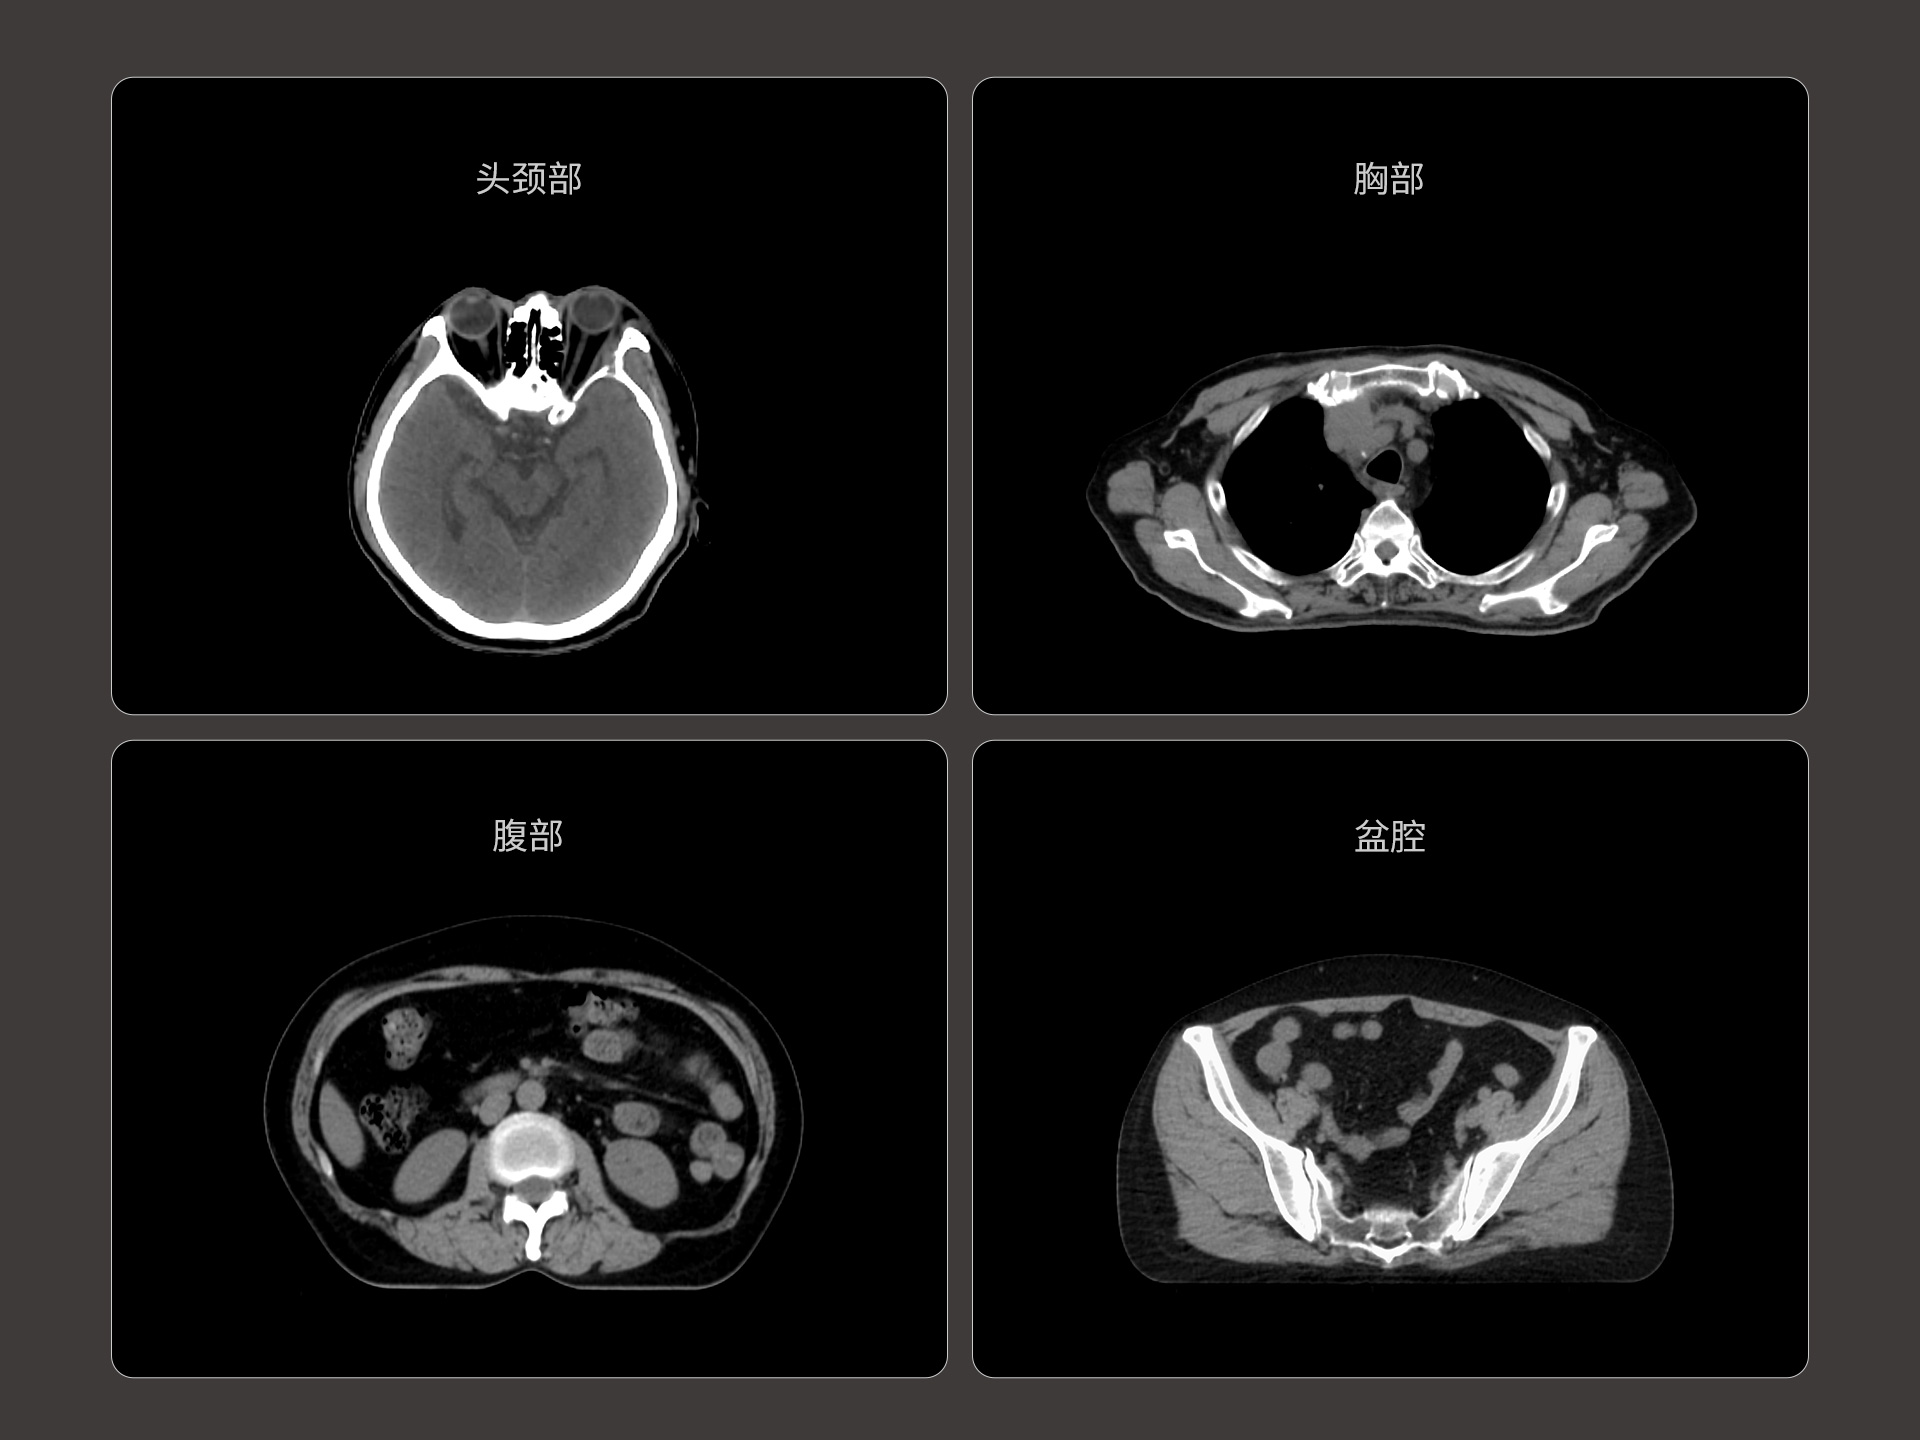

uLinac HalosTx®搭载新一代 87cm 大孔径诊断级CT图像引导系统,全能进阶,实现高清图像质量和全景视野的完美平衡,开辟全疗程 「影像感知」 ,为临床提供更自信、更全面的临床依据。

扇形束成像,极低散射,媲美CT-sim的影像品质

3mm @ 0.3% 高软组织对比度,0.55mm薄层扫描,精确鉴别肿瘤靶区边界

精准CT值,完美满足勾画、剂量计算要求

提供传统 的CT 模拟机所一致的HU值精度(±10HU)

87cm CT影像孔径设计适配多种摆位姿势,兼顾不同体型患者

标准视野 63cm,避免扫描信息缺失

轴向视野 91cm,轻松实现长靶区扫描

全景视野